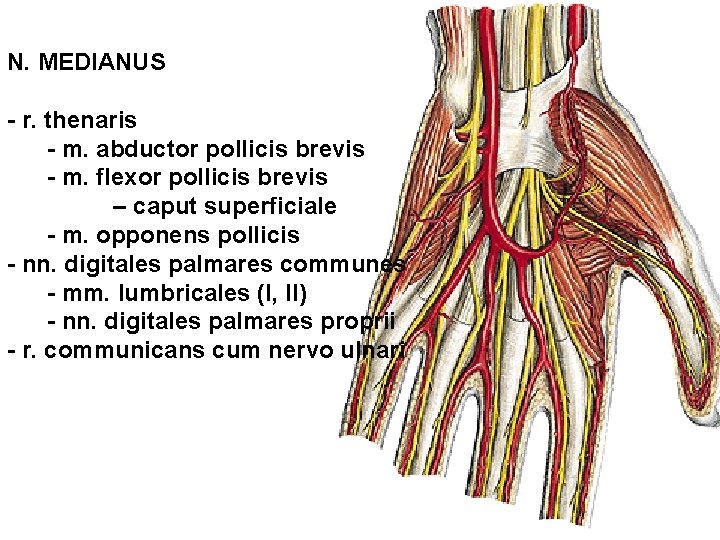

N. MEDIANUS - r. thenaris - m. abductor pollicis brevis - m. flexor pollicis brevis – caput superficiale - m. opponens pollicis - nn. digitales palmares communes - mm. lumbricales (I, II) - nn. digitales palmares proprii - r. communicans cum nervo ulnari